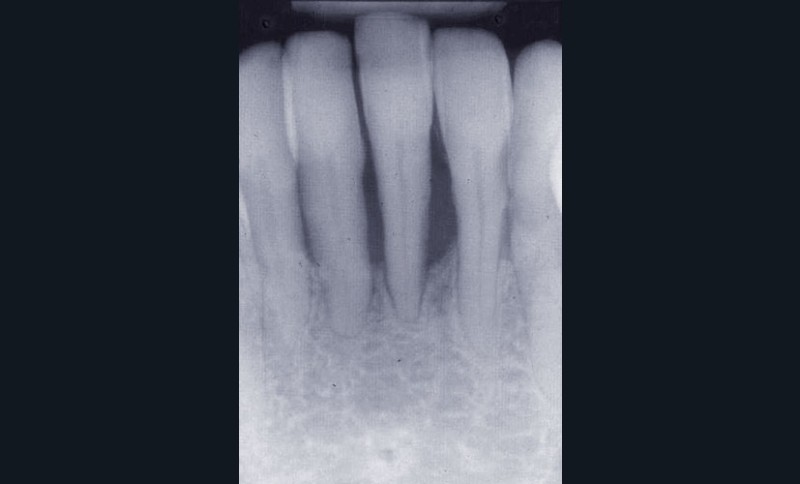

Une patiente âgée de 45 ans consulte à la fin des années 1990 avec une contention en échelle au maxillaire afin de soulager les mobilités des dents antérieures.

Les examens cliniques et radiographiques montrent une parodontite chronique généralisée (fig. 1a à m).